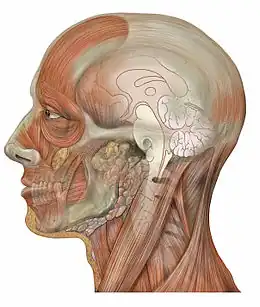

Muscles et vaisseaux de la face

Muscles et vaisseaux de la face Coupe sagittale